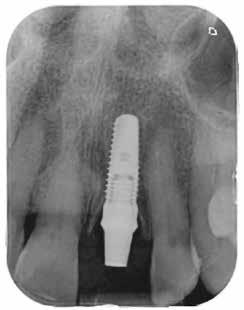

1. kép: A behelyezett implantátum röntgenképe közvetlenül a műtét után… – 2. kép: … és négy hónap gyógyulás után az ideiglenessel

A 64 éves hölgypáciens esztétikus pótlást kívánt 21-es foga helyén, amelyet balesetet követően 2022-ben távolítottak el. Az összes foga egészséges és vitális volt, így a 21-es régióba implantátum került, amelyre cirkónium-dioxid koronát terveztünk. Az implantátum típusát, pozícióját, átmérőjét egyedi anatómiai adottságainak és az adott helyviszonyoknak megfelelően választottuk meg.

Előkezelés

2023 elején került behelyezésre a 21-es régióba egy Camlog Tissue Level implantátum, 4,3 mm átmérővel és 13 mm hosszal. Az eseménymentes gyógyulást követően az implantátum csontosodását a Periotest-eljárással ellenőriztük, majd hagyományos zárt kanalas lenyomatvétel után ideiglenes ellátás készült (2–4. képek).